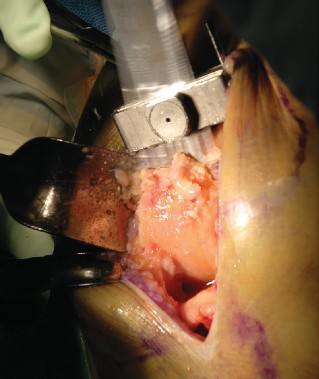

The most ubiquitous approach for TKA is the medial parapatellar arthrotomy. A straight, anterior longitudinal skin incision is made, extending from just proximal to the superior pole of the patella to just medial to the tibial tubercle. Full-thickness fasciocutaneous flaps are elevated to preserve the subdermal vascular plexus. The arthrotomy is then initiated through the medial retinaculum, coursing proximally into the quadriceps tendon (leaving a small medial cuff for later repair) and distally along the medial border of the patella and patellar tendon.

Once the joint is entered, the patella is either everted laterally or laterally subluxated, depending on the surgeon's preference and the stiffness of the extensor mechanism. A meticulous synovectomy and excision of the infrapatellar fat pad (Hoffa's fat pad) are performed to enhance visualization of the lateral compartment and the tibial plateau. All peripheral osteophytes on the femur and tibia must be aggressively resected at this stage. Retained osteophytes will artificially tension the collateral ligaments, leading to erroneous gap balancing and postoperative stiffness.